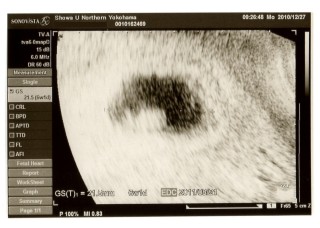

6週1日目/GS=21.5㎜ 心拍を始めて確認できた日のエコーです。 7週目と思っていたら、6週目と言われました。ナゾ。次回、先生に聞いてみようと思います。

胎嚢10ミリ 赤ちゃん2.2ミリ

6wに入ってすぐ、つわりが出始めました。 卵黄嚢と胎芽がみえ、拡大してもらうと心拍も確認できました。 次回は二週間後、成長が楽しみです。里帰り出産のため、里帰り先の産婦人科に電話しました。人気のある病院はすぐに埋まってしまうので、大体の予定日が決まればすぐに電話した方がいいみたいです。